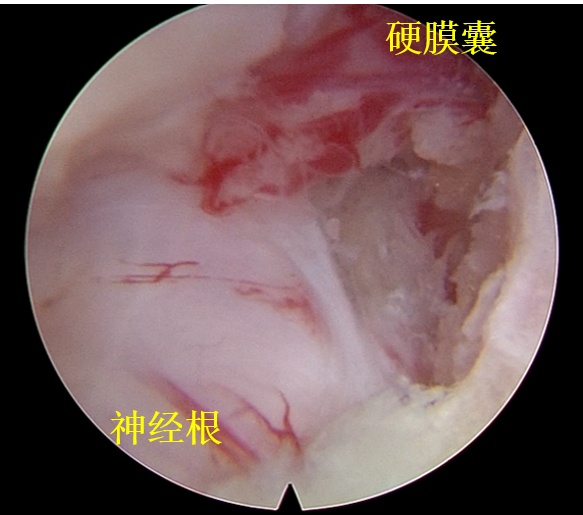

术中视野佳

该技术采用冷光源照明,且可放大成像,有利于术中操作。纤维内窥镜手术视野清晰,对于椎间盘突出。外侧黄韧带局部肥厚以及椎间孔狭窄的颈椎病患者均适用。